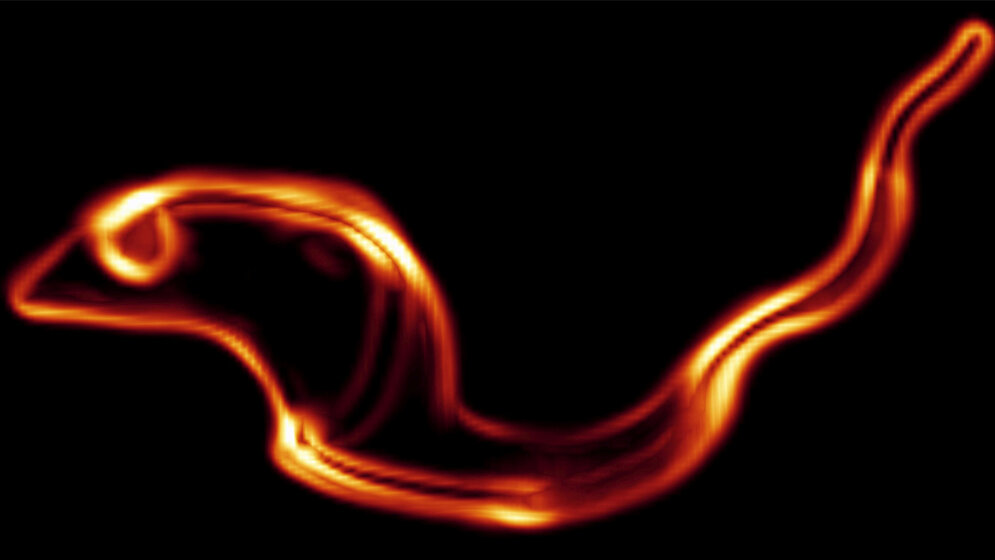

Die lebensbedrohliche Afrikanische Schlafkrankheit wird von einzelligen Parasiten ausgelöst, den Trypanosomen. Ein Team am Biozentrum der Universität Würzburg erforscht die Erreger und meldet jetzt spannende Neuigkeiten: Die Trypanosomen besitzen ein bislang unbekanntes Enzym, das es beim Menschen und anderen Wirbeltieren nicht gibt. Es ist darum ein gutes Ziel für Medikamente.

Dr. Susanne Kramer und ihre Arbeitsgruppe haben die neuen Erkenntnisse veröffentlicht. „Es handelt sich um das Enzym TbALPH1“, sagt die Forscherin. „Es setzt den Abbau der Boten-RNA in Gang und ist völlig anders als die Enzyme, die diesen Prozess bei höheren Organismen einleiten.“